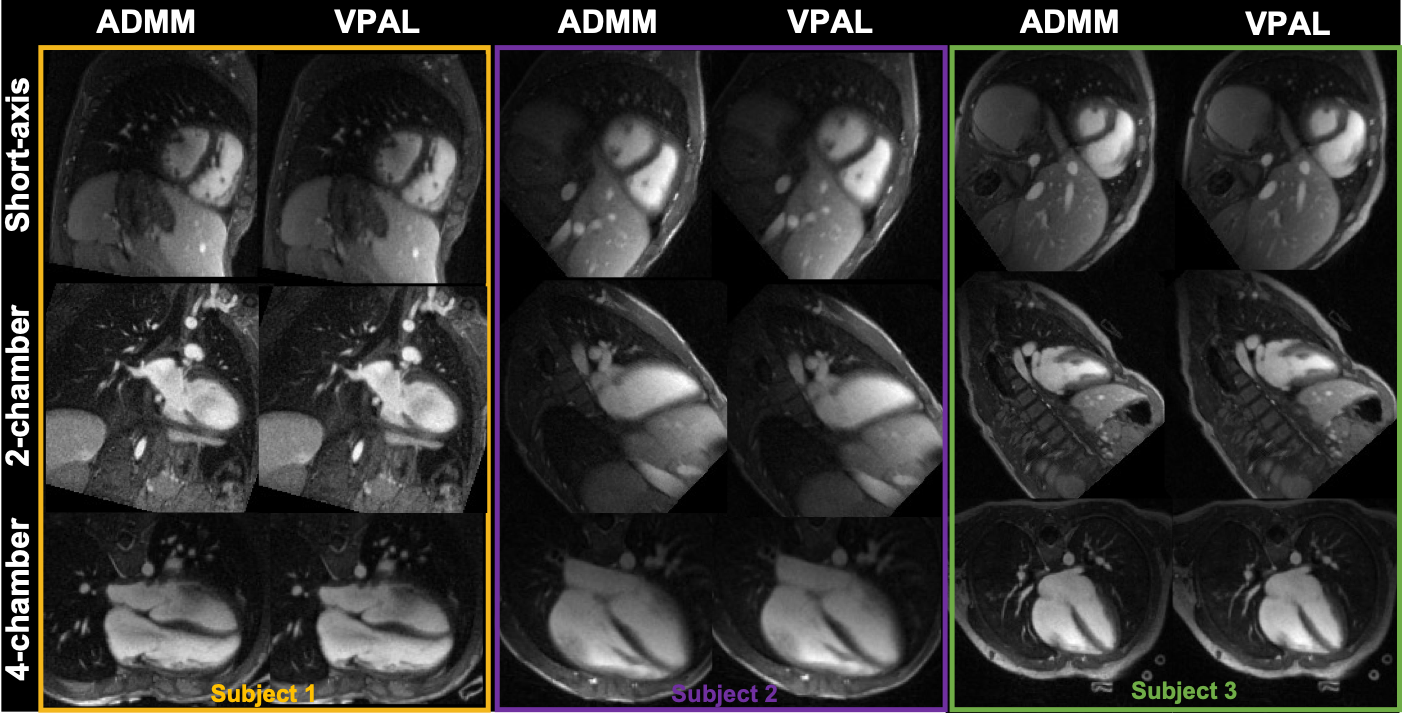

In the 15 pediatric subjects, there are a varying number of cardiac frames, 17+/4 (mean and standard deviation), and the 4 (same for all subjects) respiratory frames to be reconstructed in the 5D free-running framework. The reformatted views of three example in-vivo subjects’ ADMM and VPAL reconstructions are shown in Figure 4.

Figure 4: Exampe in-vivo reconstructions using ADMM and VPAL on three subjects The mid-short-axis, 2-chamber, and 4-chamber view in cardiac resting phase demonstrated in the output of the reconstructions using ADMM and VPAL algorithms.